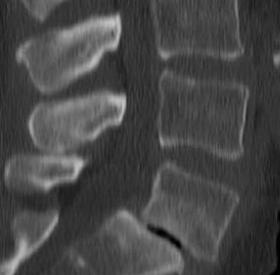

Spondilolistesi istmica

La spondilolistesi istmica è una patologia caratterizzata dallo scivolamento di un corpo vertebrale rispetto a quello sottostante (fig.1). A differenza della forma degenerativa, compare nell'infanzia o nell'adolescenza, a causa di una spondilolisi (fig.2). Con tale termine…